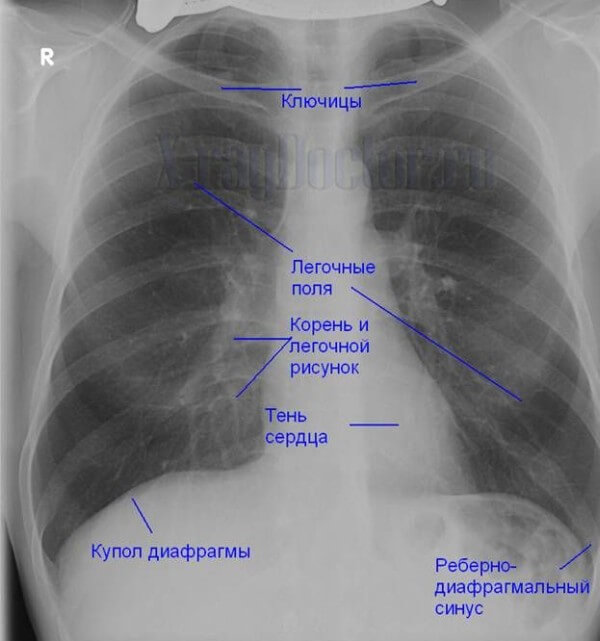

После проведения рентгенографии снимки должен изучить специалист, и на основе полученных данных и результатов других исследований сделать соответствующие выводы и поставить диагноз. В норме легкие и бронхи человека выглядят следующим образом:

- легочные доли имеют одинаковый, равномерный черный оттенок;

- в районе сердца наблюдается белый просвет;

- ребра и ключицы серые, с привычными очертаниями;

- купола диафрагмы белого цвета;

- позвоночный столб расположен в центре.